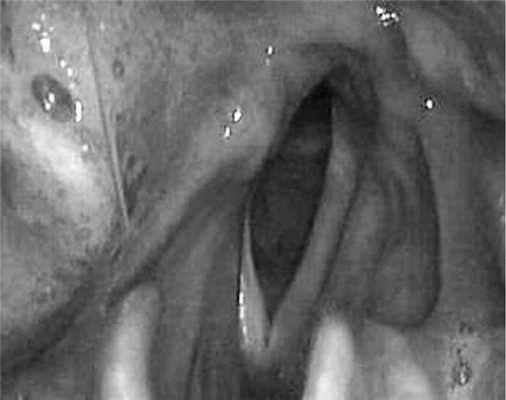

Односторонний паралич суживает просвет гортани наполовину, клинически проявляясь одышкой при физической нагрузке. Голосовая функция при этом страдает незначительно, но это чрезвычайно важно людям с определенными профессиями: дикторам, певцам и т. д. Достоверно определить, поврежден ли возвратный нерв, можно только при визуальном осмотре гортани при помощи ларингоскопии (рис. 3).

Рис. 3. Парез правой половины гортани (ларингоскопия).